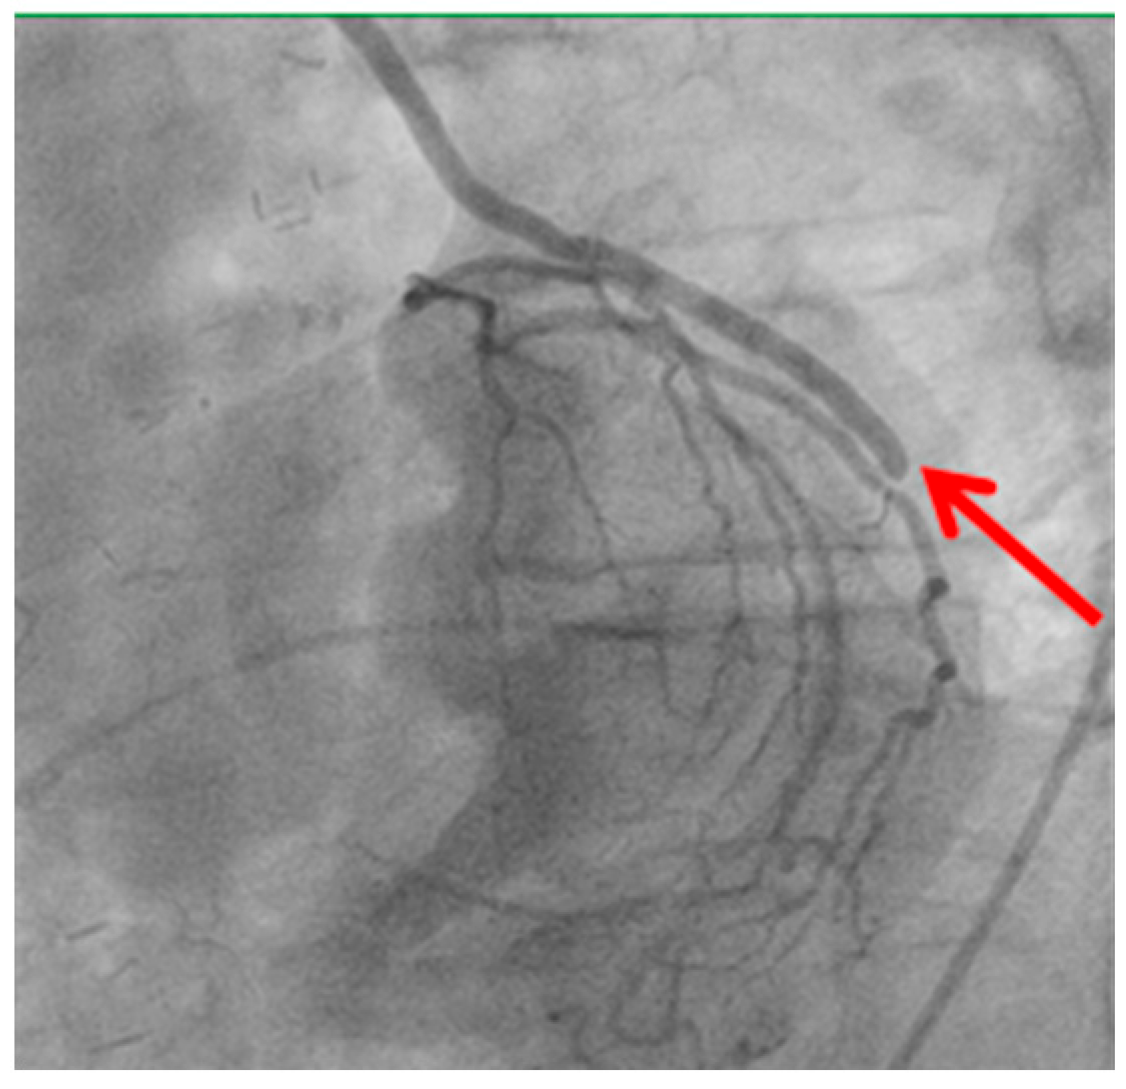

Technical issues remain a principal cause of PMI, with early graft thrombosis or occlusion being leading indications for uCAG (Figure 1, Figure 2, Figure 3 and Figure 4 illustrate typical technical causes, including proximal anastomotic stenosis, kinking, distal anastomotic stenosis, and misplaced anastomoses). Notable contributors include anastomotic stenosis, kinking, overstretching of grafts, and temporary graft spasm [13,21]. Prueßer et al. demonstrated that 30% of PMI cases detected via CAG were graft-related failures [13]. In this context, uCAG often reveals technical failures immediately post-surgery, providing the advantage of guiding targeted percutaneous coronary intervention or revascularization. Graft spasm, which can be relieved by nitrates, may also lead to acute ischemia. It refers to the temporary constriction of the bypass graft, reducing blood flow to the myocardium. This condition can be caused by various factors, including surgical trauma, inflammation, or the release of vasoactive substances [21].

Image illustrating an anastomosis performed before a significant vessel stenosis (shown by the red arrow). Suboptimal graft positioning or incomplete revascularization can contribute to ongoing myocardial ischemia and increase the likelihood of uCAG.

Figure 4. Anastomosis performed before the vessel stenosis.